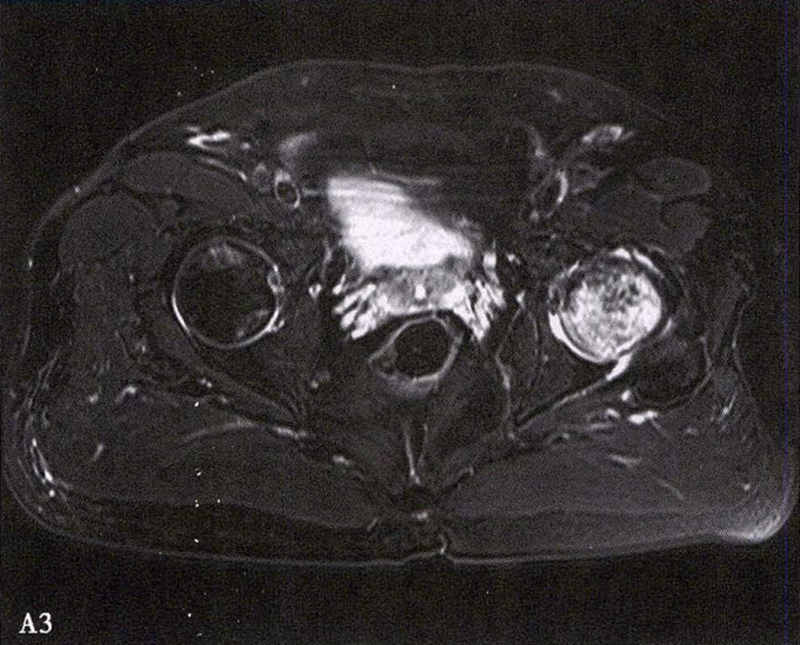

(2)MRI检查 MRI检查是早期诊断股骨头坏死最具特异性、灵敏度的检查方法。当怀疑有股骨头坏死,而X线片无明显异常时,应行MRI检查。诊断时可根据髋关节X线、MRI显示的坏死面积和塌陷程度进行ARCO分期。

冠状面及横断面MRI图像

MRI示双侧股骨头坏死,冠状面显示右侧股骨头坏死(图A、C),横断面显示双侧股骨头坏死(图B、D);T1加权像(图A、B)显示硬化带为低信号,T2加权像(图C、D)显示右侧骨坏死硬化带外围高信号的骨髓水肿,左侧无骨髓水肿。

A.男性,71岁,双侧股骨头坏死,右侧Ⅰ期、左侧Ⅲ期。X线片示双侧股骨头形态可,右股骨头未见明显密度改变,左股骨头关节面下见局限性骨密度减低及增高区(A1)。MRI(T2加权像)示右股骨头内双线征,左侧不规则形混杂信号,坏死区远端骨髓水肿(A2、A3)。